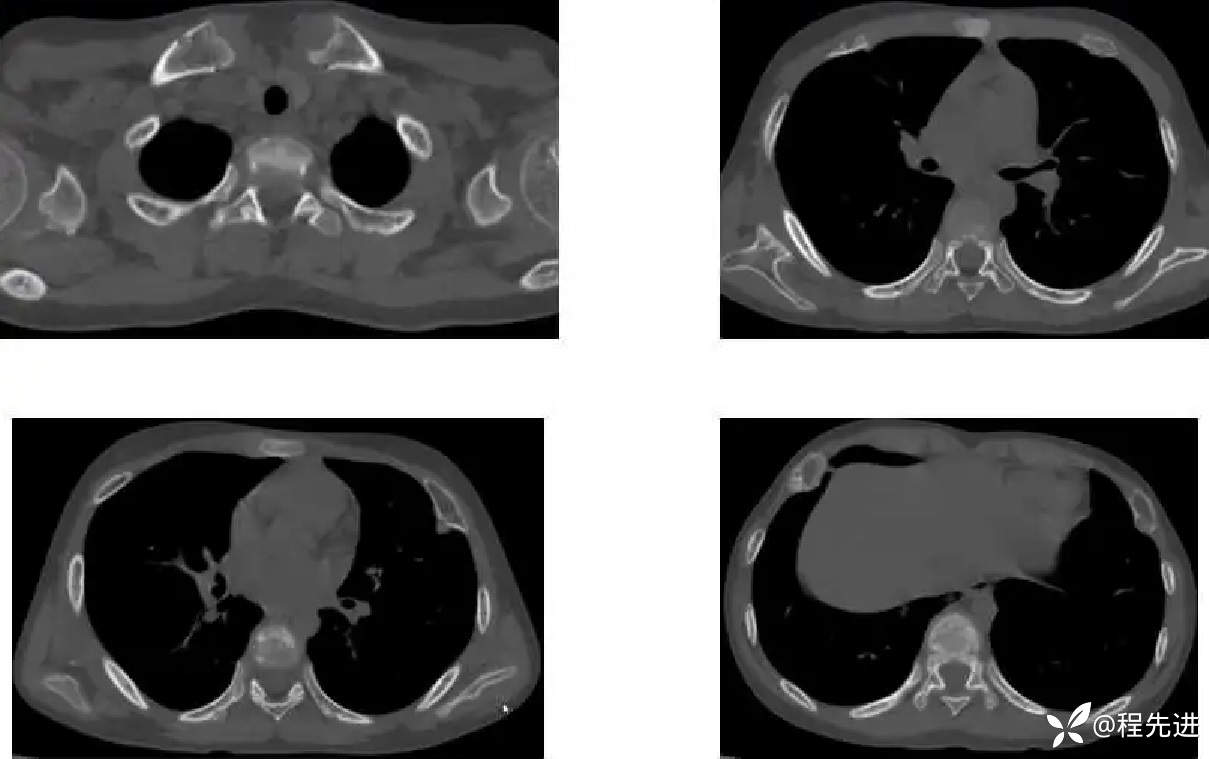

患者性别:男

患者年龄:11岁

简要病史:受凉后发热3天

既往史:生长发育迟缓

胸部CT: